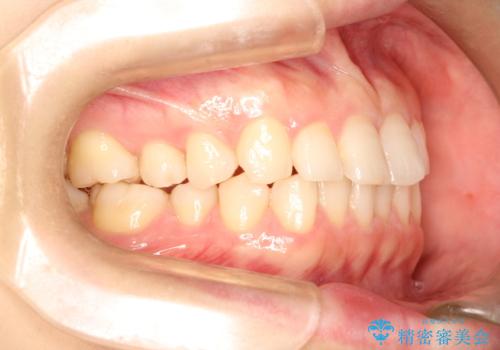

- 前歯のガタガタを綺麗にしたいとのことでインビザラインにて治療を行いました。

治療前は臼歯部反対咬合のため下顎が偏移し正中がずれていましたが、臼歯部反対咬合を改善したことで、正中のズレを改善することができました。